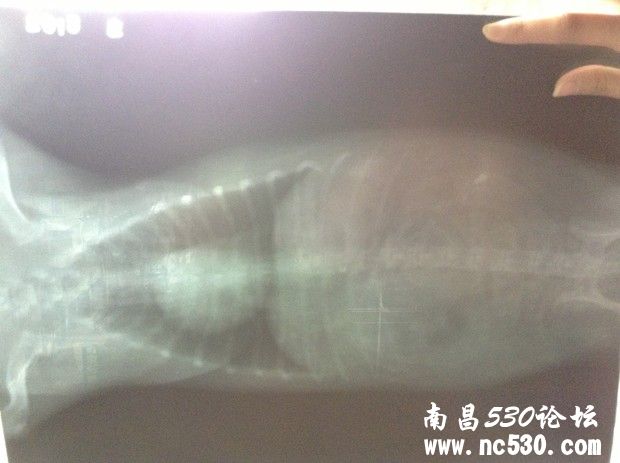

狗狗咳嗽已好几个月,之前一直是偶尔一两声卡卡干咳声,到最近转变成一连串咳嗽,明显加重,而且咳嗽声音变化了。前天带去医院看,打了X光,查了血常规和电解质(这个查没查我不知道医生也没说但收了费)。然后医生说心脏有点点肥大,应该是心脏顶到气管造成的咳嗽。别的血常规这些都正常,血压也正常。就说以后给它吃皇家心脏处方狗粮,然后开了几颗扩张支气管的药(肺心康),两三天的量。就这样了。但是狗狗回来还是一直咳,特别是晚上,咳得很可怜,咳到最后还象卡痰那样的象有痰吐不出来似的。我就是想知道,我家狗狗到底是不是因为心脏原因引起的咳嗽,还是会是别的原因?难道就让它这么咳下去么?皇家心脏处方狗粮现在买不到,还是吃的平常的,因为说它有点点偏胖就给它吃得很少减了量。它现在饿跑来想吃我都不敢给它吃,请问这样让它少吃的做法对么?还是吃一般的狗粮可以么?

还有就是今天回来仔细看片子,发现下图那块(喉咙还是气管那下面我圈起来的地方)有块东西,也不知道是片子是脏的还是它身上的?特意放上来请各位专家医生看看。说实话,那天医生也没和我讲清楚,连查血那些的单子也没给我,病历也未给写,片子我还是走的时候要求要的。